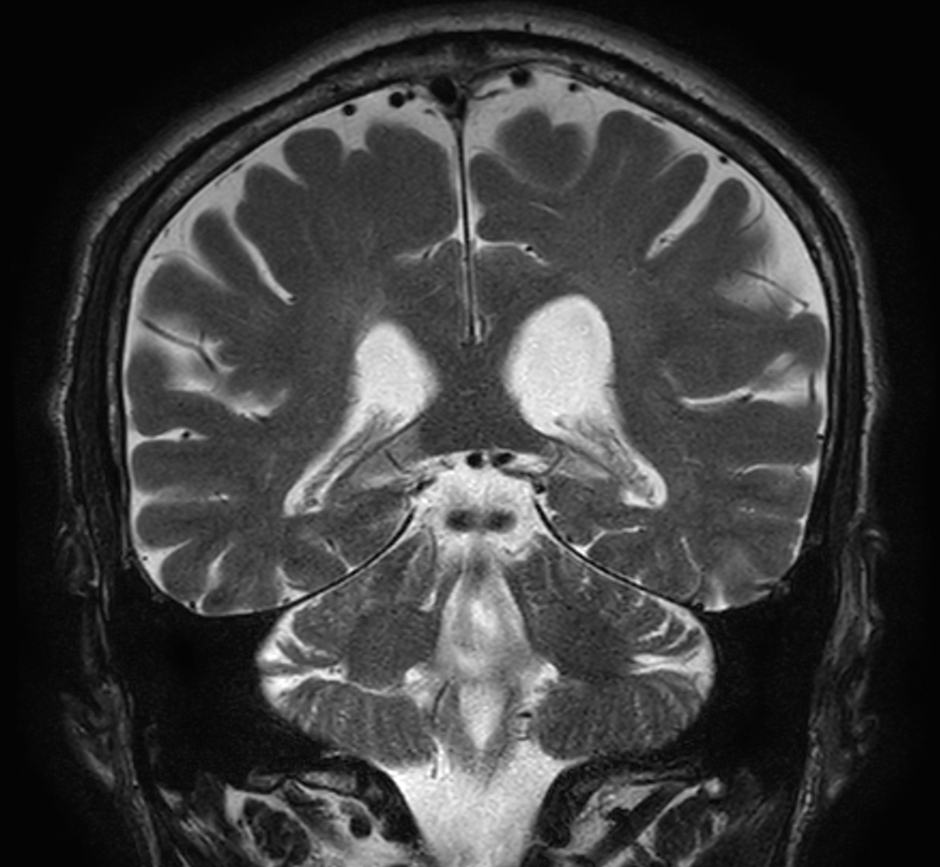

뇌 MRI(Magnetic Resonance Imaging)는 강한 자기장과 라디오파를 이용해 뇌의 구조와 기능을 고해상도로 촬영하는 영상검사입니다. 방사선을 사용하지 않으며, 연부조직 표현력이 뛰어나 뇌신경계 질환의 조기 진단에 매우 효과적입니다.

뇌 MRI로 진단 가능한 주요 질환

- 뇌종양: 위치, 크기, 성질 확인

- 뇌출혈 및 뇌경색: 허혈성 및 출혈성 병변 확인

- 치매: 뇌 위축 및 혈류 감소 확인

- 다발성경화증: 신경계 염증성 질환 진단

- 기형 및 낭종: 선천적 구조 이상 확인

- 뇌동맥류: 필요 시 조영제 활용해 혈관 촬영 가능